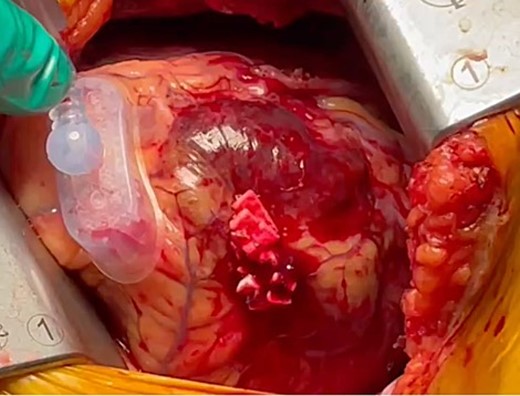

The patient was positioned by elevating in a 30° to 40° right lateral decubitus position to facilitate a widened intercostal space. The patient was intubated with a double-lumen endotracheal tube. A 10 cm left mini-thoracotomy was performed in the fourth intercostal space, with 1/3 of the incision medial to the mid-clavicular line. The ThoraTrak® MICS Retractor System (Medtronic Inc., MN, USA) was employed to achieve optimal access to the left chest and effectively visualize the internal mammary arteries. The LITA was harvested in a skeletonized fashion under direct vision, and the saphenous vein (SVG) was harvested from the right leg. To maintain the activated clotting time > 280 s, heparin (1 mg/kg) was administered after the LITA harvest. In this case, the Tentacles NEO (Sumitomo Bakeride, Akita, Japan) was used as a heart poisoner and cardiac stabilizer. We made four distal anastomoses (LITA-LAD, Aorta-SVG1-first diagonal, Y-composite SVG2-OM- posterolateral artery). When one of the suction cups attached to the apex of LV was detached, an epicardial hematoma was coming at the attachment site (Fig. 2). This bleeding point was repaired by continuous suture by 4–0 prolene with two big felt. After protamine was given, good hemostasis was achieved (Fig. 3).

The bleeding spot was repaired using a continuous suture with 4–0 prolene and two large felts. Following the administration of protamine, effective hemostasis was achieved.